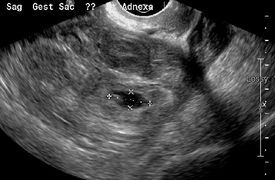

Transvaginal ultrasonography

An ultrasound showing a gestational sac with fetal heart in the fallopian tube has a very high specificity of ectopic pregnancy. Transvaginal ultrasonography has a sensitivity of at least 90% for ectopic pregnancy.[1] The diagnostic ultrasonographic finding in ectopic pregnancy is an adnexal mass that moves separately from the ovary. In around 60% of cases, it is an inhomogeneous or a noncystic adnexal mass sometimes known as the "blob sign". It is generally spherical, but a more tubular appearance may be seen in case of hematosalpinx. This sign has been estimated to have a sensitivity of 84% and specificity of 99% in diagnosing ectopic pregnancy.[1] In the study estimating these values, the blob sign had a positive predictive value of 96% and a negative predictive value of 95%.[1] The visualization of an empty extrauterine gestational sac is sometimes known as the "bagel sign", and is present in around 20% of cases.[1] In another 20% of cases, there is visualization of a gestational sac containing a yolk sac and/or an embryo.[1] Ectopic pregnancies where there is visualization of cardiac activity are sometimes termed "viable ectopic".[1]

The combination of a positive pregnancy test and the presence of what appears to be a normal intrauterine pregnancy does not exclude an ectopic pregnancy, since there may be either a heterotopic pregnancy or a "pseudosac", which is a collection of within the endometrial cavity that may be seen in up to 20% of women.[1]